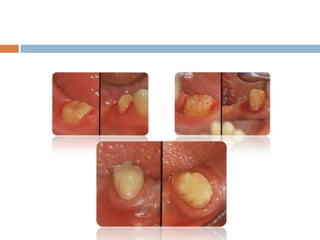

This document discusses common problems that can occur with crowns and bridges (C&B) and their solutions. It covers issues with impressions, frameworks, cementation and clinical/laboratory techniques. Some key points: - Impression problems like voids, tears or lack of detail can result in poor fitting restorations. Solutions include improving retraction, moisture control, and using appropriate materials and techniques. - Framework issues like porcelain fractures, solder joint failures or distortion can cause restorations to fail. Rounding internal line angles, ensuring adequate porcelain thickness/support, and preventing flaws can help. - Changes in abutment teeth over time from issues like periodontal disease, caries or